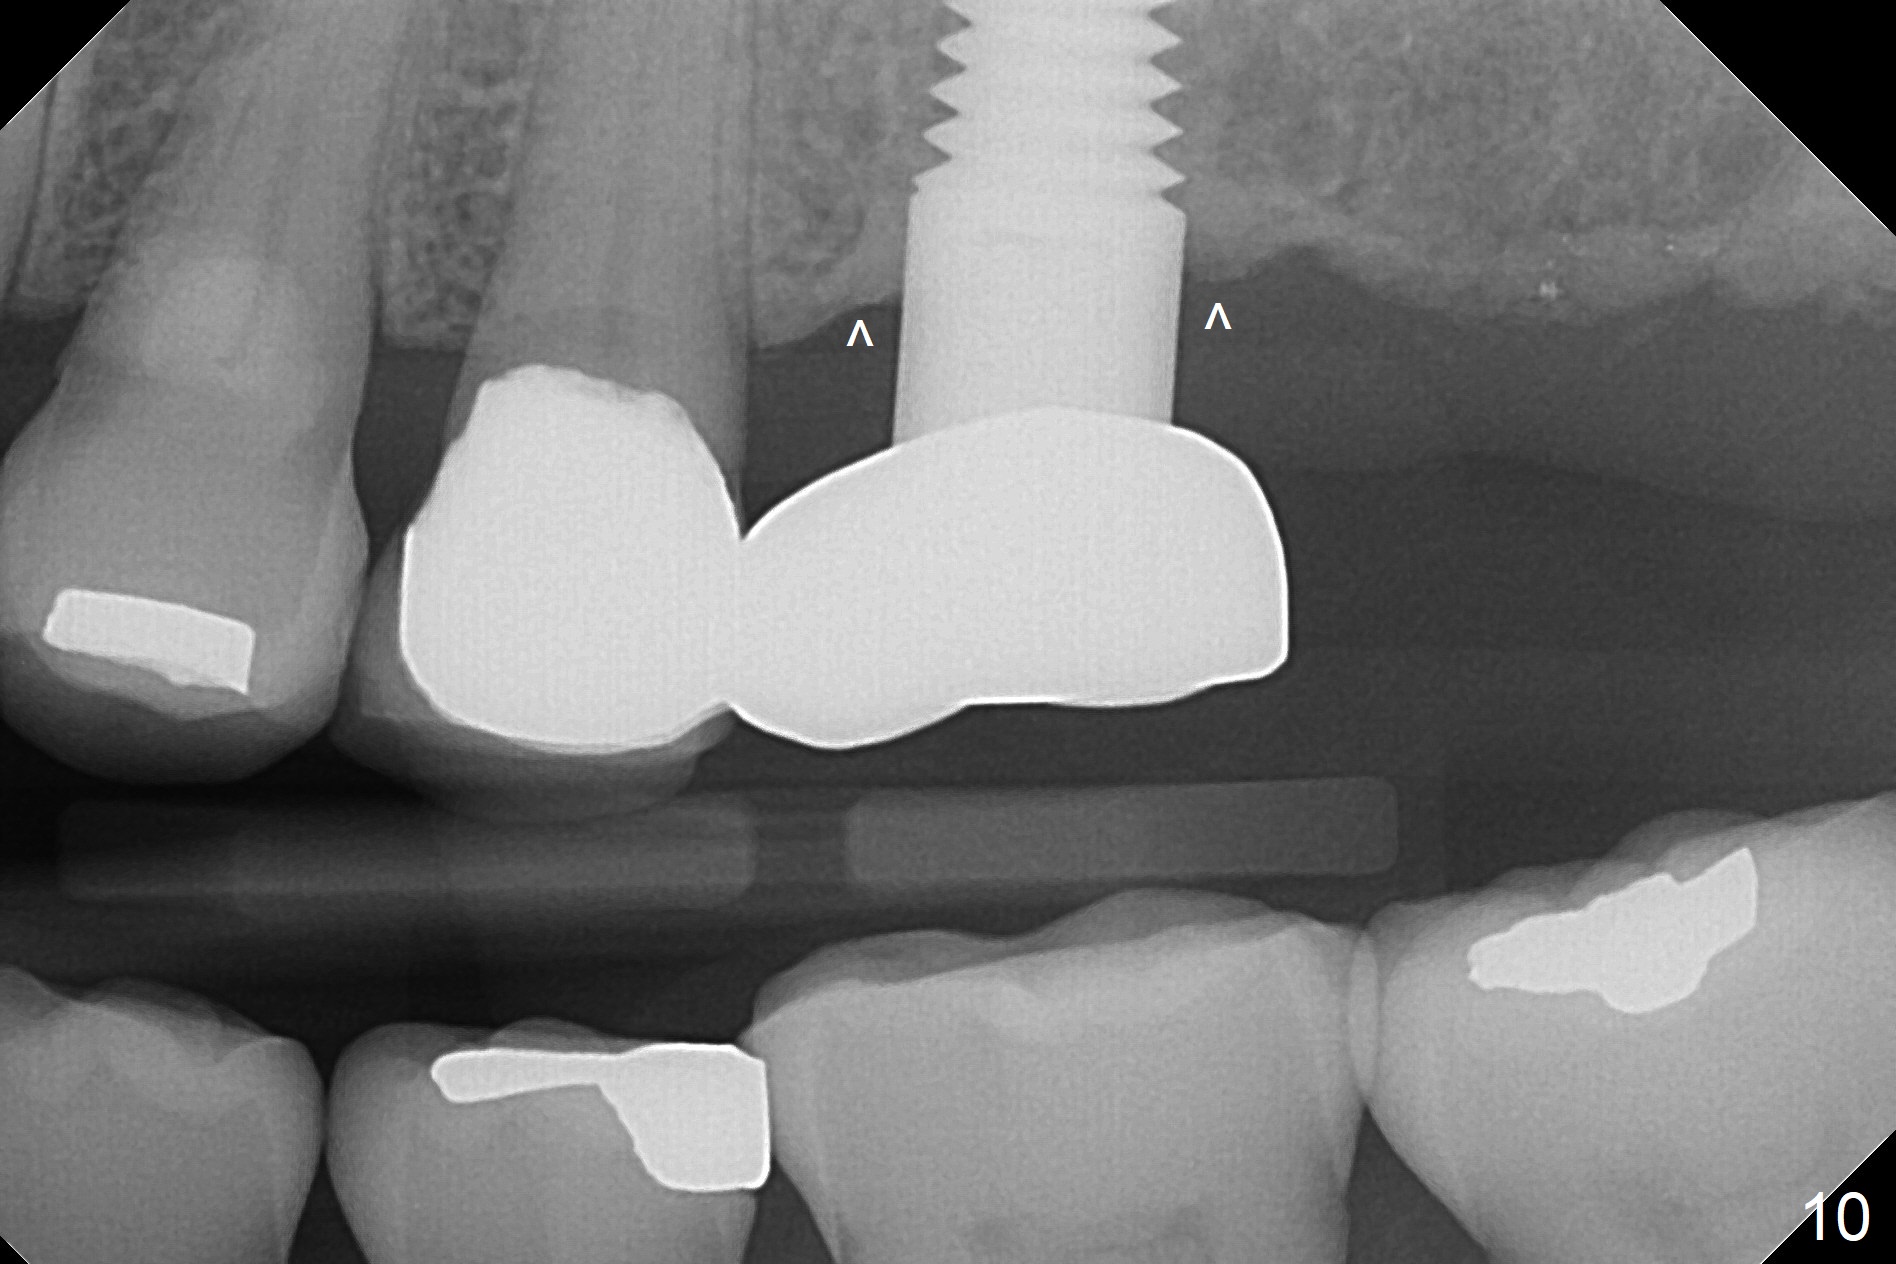

One year 2 months post cementation, the patient complains of inability to chew on the left. It appears that the crown at the site of #14 (Fig.8) is not as large as the tooth #3 (Fig.7); the occlusal contact of the crown is less than that of the tooth #3. The complaint remains the same after crown being remade. It appears that implant at #15 is needed (Fig.9: 1 year 9 months post cementation of #14 crown). The crestal cortical bone is thicker around the implant 2 years 4 months post cementation (Fig.10).